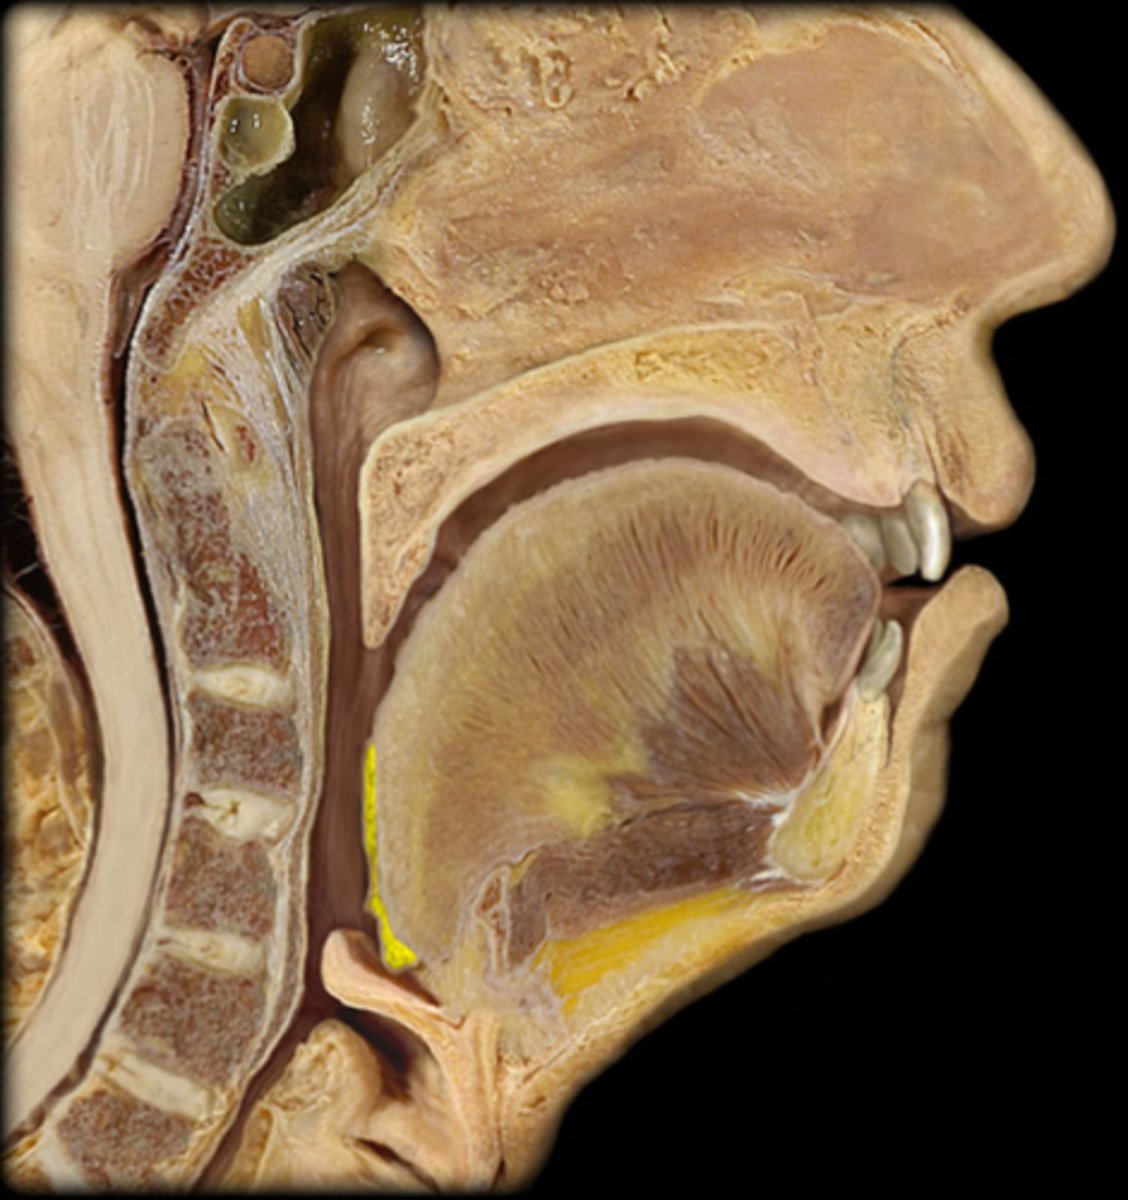

lingual tonsil

palatine tonsil

pharyngeal tonsil